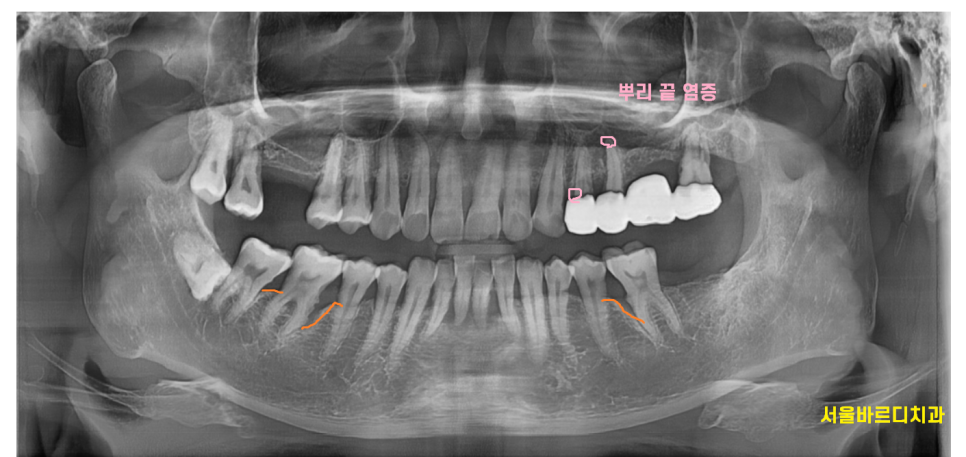

뿌리 쪽 부분은 눈으로 확인이 어렵기 때문에

x-ray를 찍지 않으면

뿌리 염증이라던가

치아 부러짐

잇몸 내려감

볼 수 있는 부분이 한계가 있습니다.